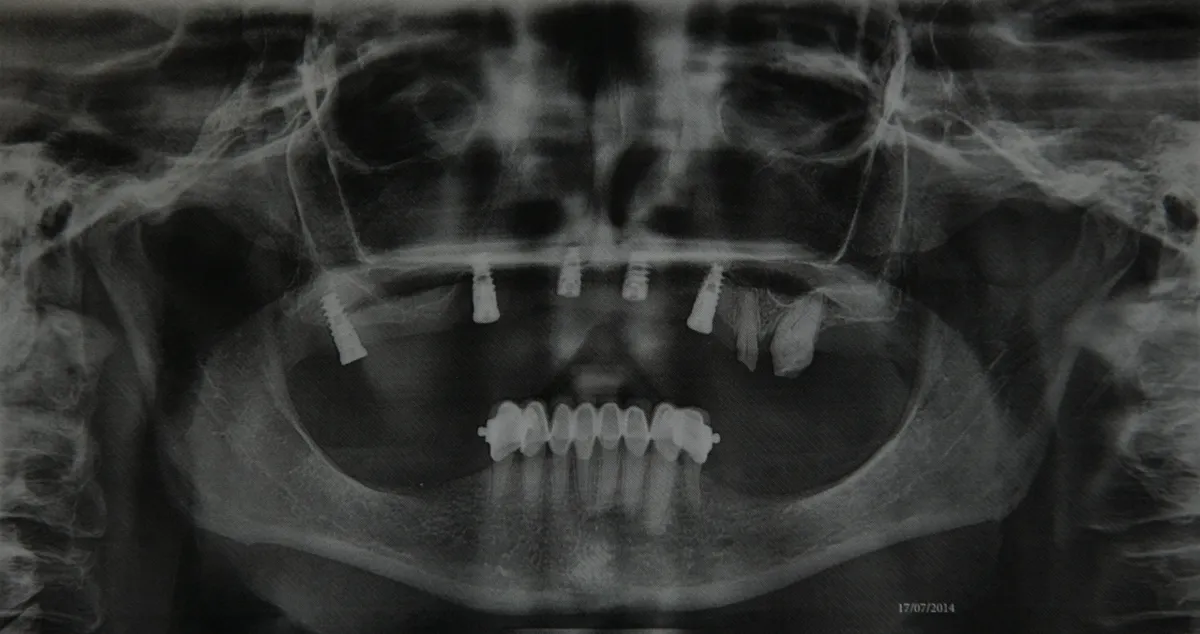

Az asszonynak még 2012-ben javasolta brit fogorvosa, hogy az esedékessé vált implantátum-beültetést ne Angliában, hanem sokkal olcsóbban, Magyarországon végeztesse el. Az özvegyasszony végül egy közvetítőcégen keresztül egy budapesti fogászaton végeztette el a beavatkozást – írja a Bors.

Az asszony angol ügyvédeivel beperelte a budapesti fogorvosokat, akik először nem ismerték el a hibájukat, most azonban megegyeztek a nővel, aki összesen 9500 fontos, azaz majdnem négymillió forintnyi kártérítést kapott.